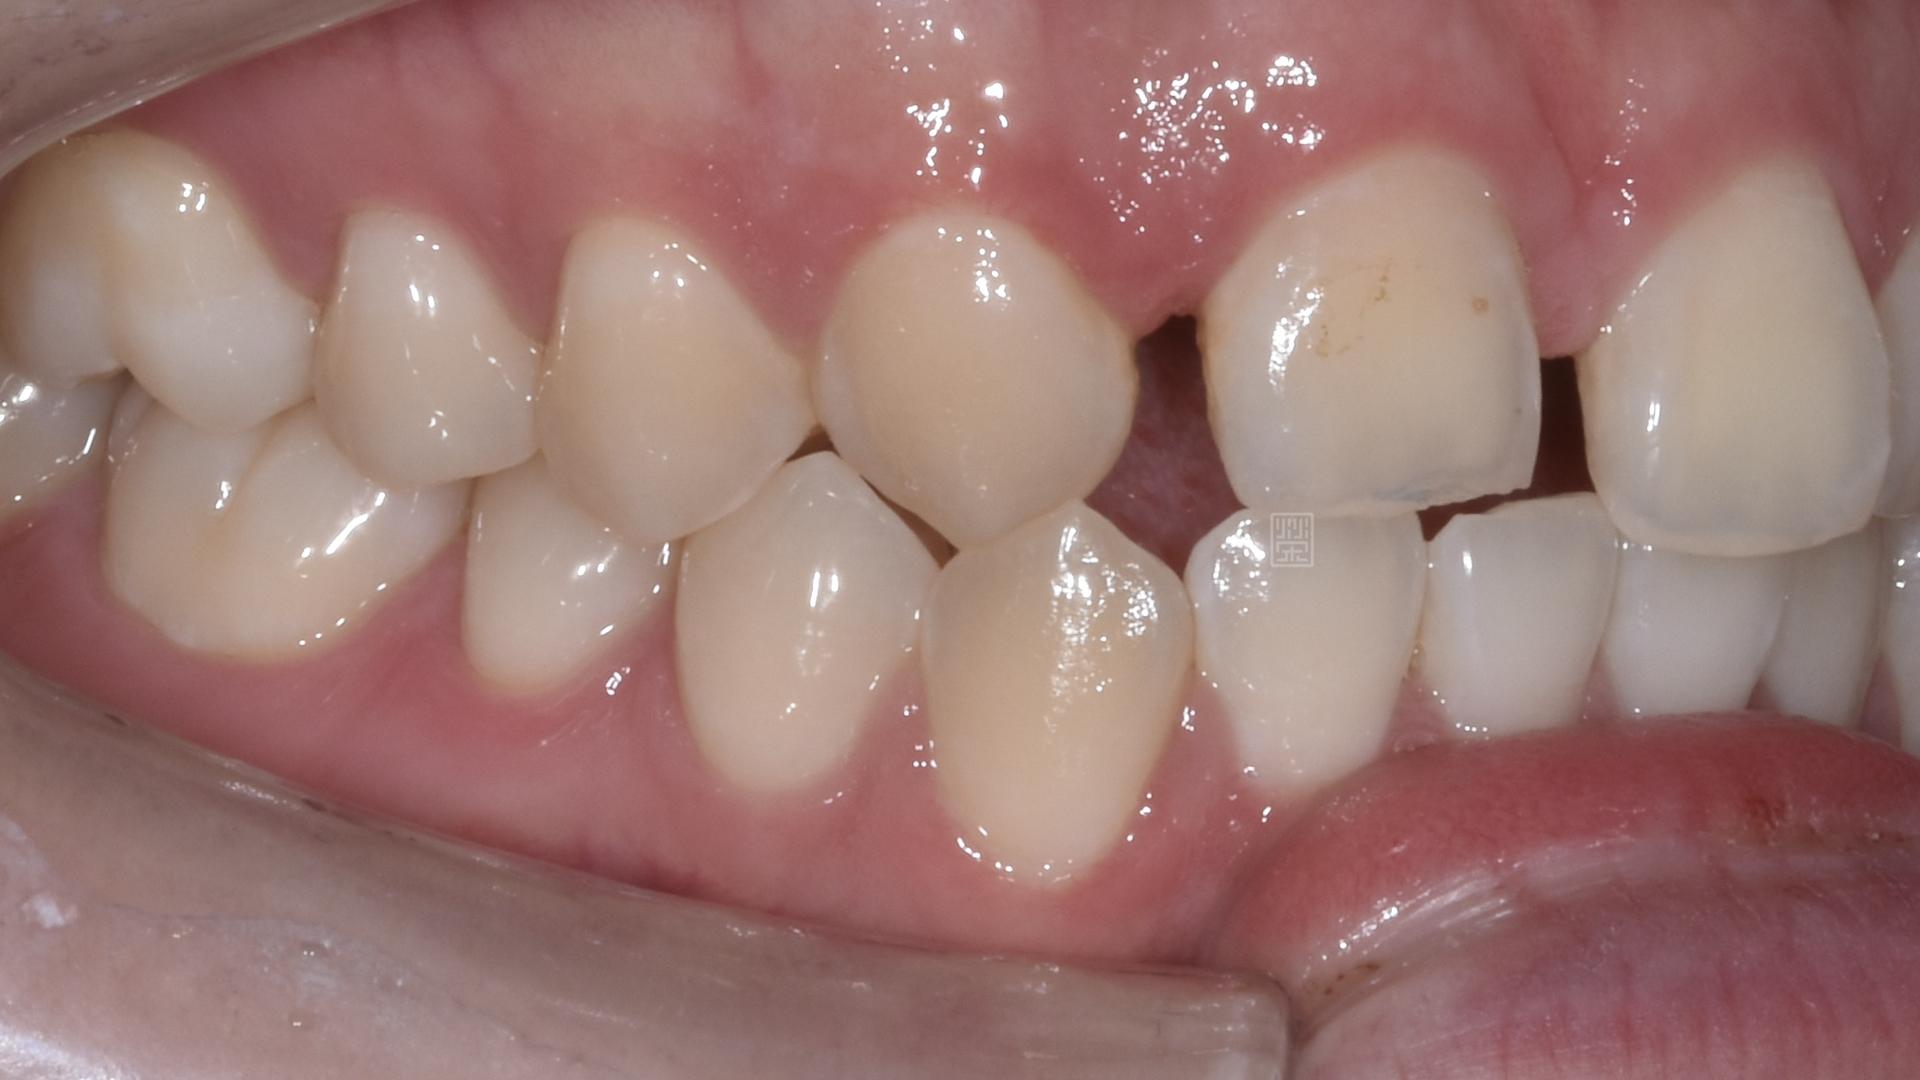

長期缺牙側門牙空間不足

治療前牙齒因車禍有縫且缺牙